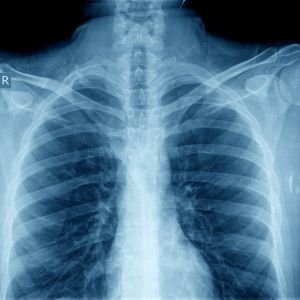

Chest X-Ray

A chest X-ray is commonly used to evaluate the lungs, heart, and ribs, helping diagnose conditions like pneumonia, tuberculosis, and lung cancer.